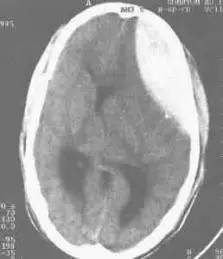

硬膜外出血CT图片

硬膜外血肿CT:呈梭形.硬膜外血肿是位于颅骨内板与硬脑膜之间的血肿,好发于幕上半球凸面,约占外伤性颅内血肿30%,其中大部分属于急性血肿,次为亚急性,慢性较少。硬膜外血肿的形成与颅骨损伤有密切关系,骨折或颅骨的短暂变形,撕破位于骨沟的硬脑膜动脉或静脉窦引起出血或骨折的板障出血,90%的硬脑膜外血肿与颅骨线形骨折有关。

CT表现:硬脑膜外血肿绝大多数(85%)都有典型的CT特点:在颅骨内板下方有双凸形或 硬膜外血肿梭形边缘清楚的高密度影,CT值40HU-100HU;有的血肿内可见小的圆形或不规则形的低密度区,认为是外伤时间太短仍有新鲜出血(较凝血块的密度低),并与血块退缩时溢出的血清混合所致;少数血肿可呈半月形或新月形;个别血肿可通过分离的骨折缝隙渗到颅外软组织下;骨窗位常可显示骨折。此外,血肿可见占位效应,中线结构移位,病变侧脑室受压,变形和移位。静脉源形硬膜外血肿因静脉压力低,血肿形成晚,CT扫描时血肿可能溶解,表现为略高密度或低密度区。少数病人受伤时无症状,以后发生慢性硬膜外血肿,这时作增强后扫描可显示血肿内缘的包膜增强,有助于等密度硬膜外血肿的诊断。